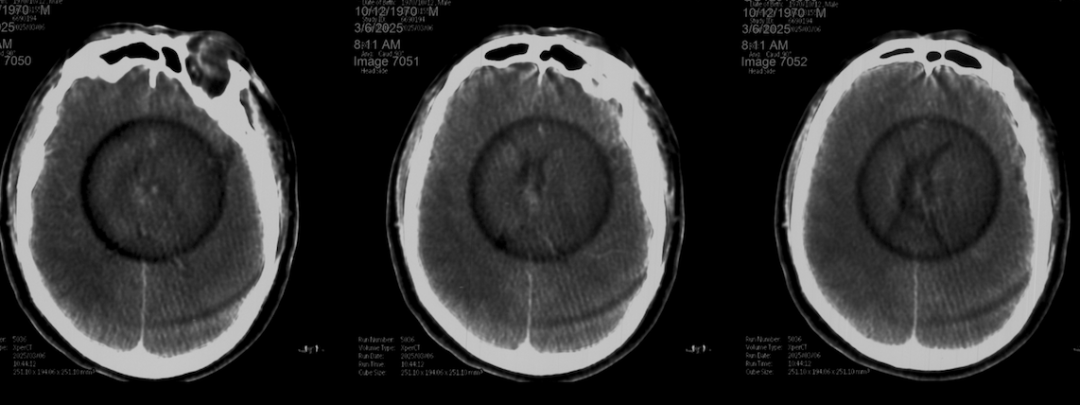

术前外院 DSA 2025-02

箭头所指右侧A1微小动脉瘤

工作位正位造影(图片)

工作位侧位造影(图片)

工作位正位造影(视频)

工作位侧位造影(视频)